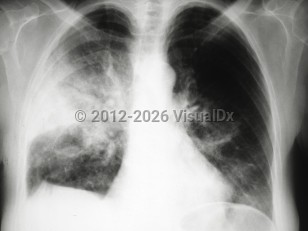

Radiographic findings are variable and nonspecific. Ground glass and reticular opacities are often seen on chest x-ray and high-resolution computed tomography (HRCT), as well as small bilateral pleural effusions.